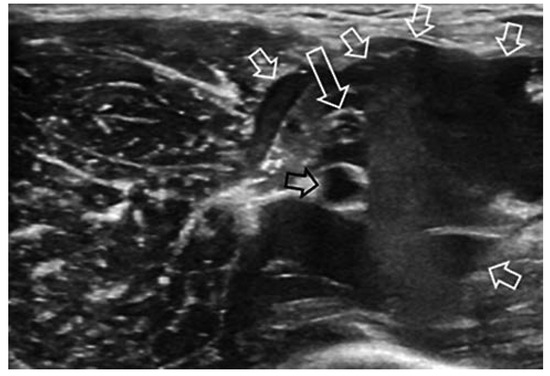

Case report A 22-year-old male experienced a presyncopal spell while studying for a university examination [...]